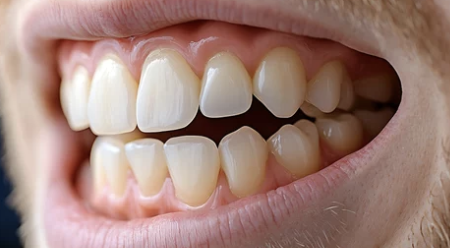

4. 잇몸 복원 치료 전후 비교 (예시 도표)

구분 치료 전 치료 후

| 치아 길이 | 길고 불규칙함 | 원래 높이로 복원됨 |

| 시림 증상 | 찬 것에 민감 | 대부분 완화 |

| 잇몸 색 | 창백하거나 붉음 | 건강한 핑크빛 |

| 음식물 끼임 | 자주 끼고 불편함 | 개선됨 |

| 미소 라인 | 비대칭 | 자연스러움 회복 |

※ 실제 결과는 잇몸 상태, 수술 방법, 개인 회복력에 따라 차이가 있습니다.